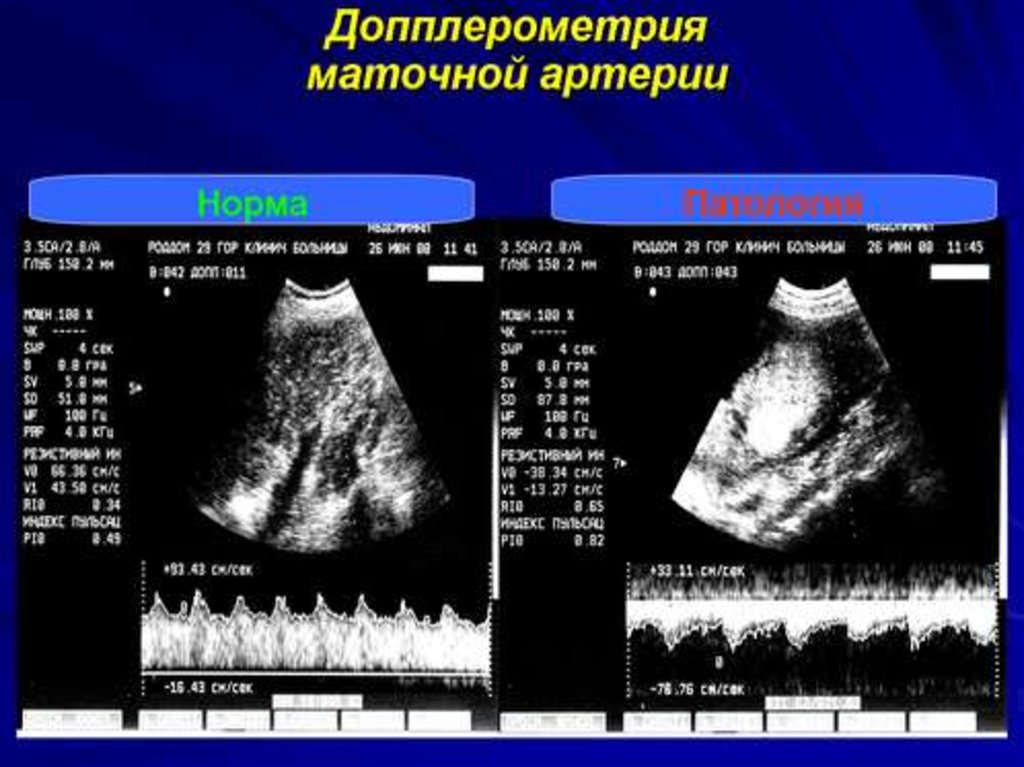

Пренатальная диагностика

1. ПРЕНАТАЛЬНАЯ ДИАГНОСТИКА